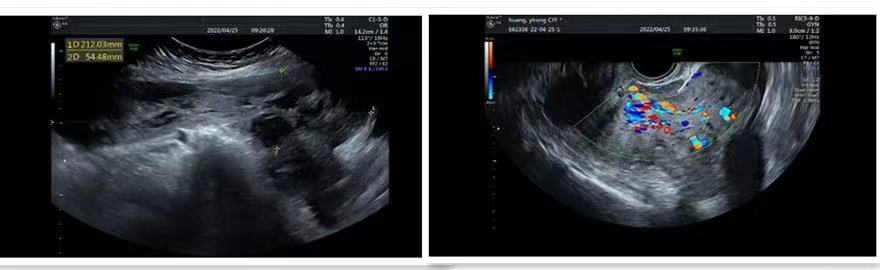

超声:右附件区探及边界清晰囊区,33mm×32mm×27mm,内可见密集点状低回声。盆腹腔内可探及巨大囊实性包块212mm×213mm×54mm,内大部分为形态不规则无回声囊区,实性区为疏松低回声,低回声团与子宫峡部剖宫产瘢痕相连,可探及宽约24mm的蒂自瘢痕处发出,包块蒂部血流丰富,RI:0.54。

盆腔巨大囊实性包块——来源于子宫?

右卵巢囊肿——巧囊?